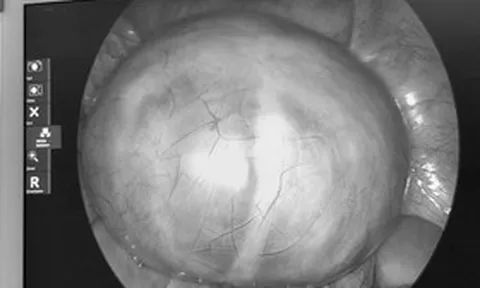

Kỳ lạ cô gái 22 tuổi có 3 quả thận

Một phụ nữ 22 tuổi ở Đà Nẵng được bác sĩ phát hiện dị tật bẩm sinh hiếm. Theo các bác sĩ, những trường hợp có 3 quả thận chỉ chiếm 1% dân số. Bệnh có thể gây nhiễm trùng tiết niệu tái phát, tiểu buốt, tiểu rắt, đau vùng hông lưng.